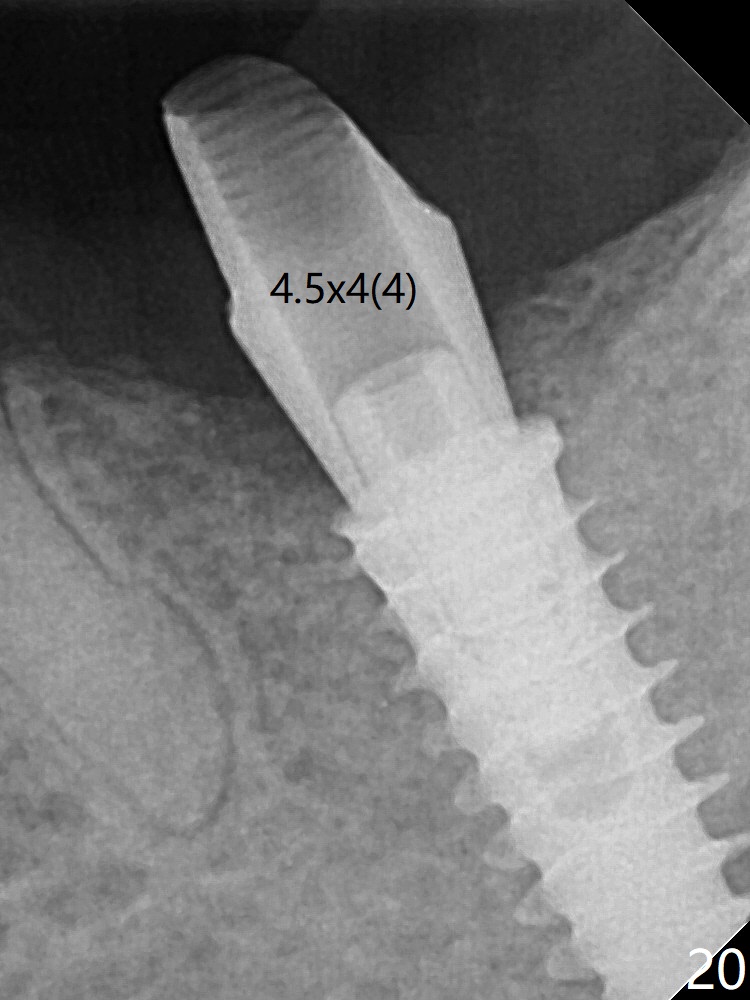

术后四个月伤口愈合,骨粉几乎没有丢失(图十九:*)。切开,刮匙去骨,有一定硬度,即刻放置修复基台,完全就位(图二十),制备临时牙冠,牙周敷料固定组织瓣(没有缝线)。术前